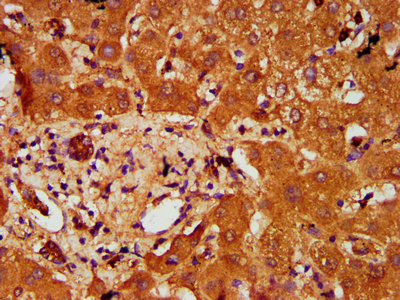

IHC image of CSB-PA769809LA01HU diluted at 1:200 and staining in paraffin-embedded human liver tissue performed on a Leica BondTM system. After dewaxing and hydration, antigen retrieval was mediated by high pressure in a citrate buffer (pH 6.0). Section was blocked with 10% normal goat serum 30min at RT. Then primary antibody (1% BSA) was incubated at 4°C overnight. The primary is detected by a biotinylated secondary antibody and visualized using an HRP conjugated SP system.